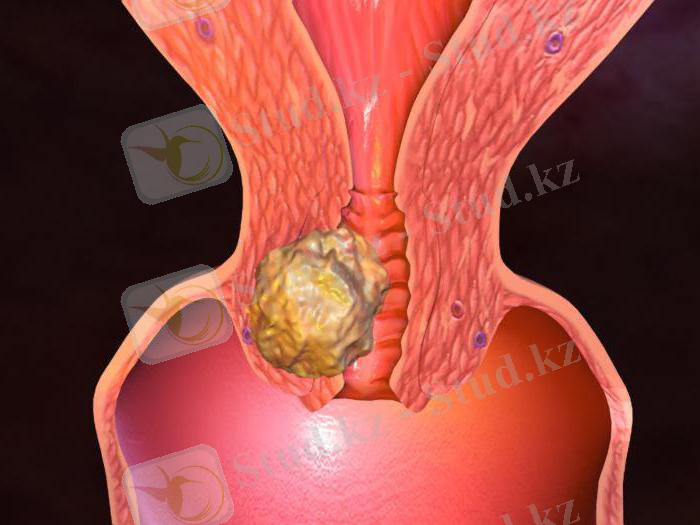

Лейомиомалар. Ішкі ағзаларда түзіледі (ішек - қарын жолында) . Жатырда фибромиомалар жиі кездеседі - бұл фиброзаға ұшырайтын лейомиомалар.

Тератома деп ұрық клеткаларынан пайда болатын әртүрлі тіндерден түзілген ісікті атайды. Олар сегізкөз-құймшақ аймағында, көкірек қуысында, құрсақ пердесі сыртында, аналық және аталық бездерде, бас сүйегі ішінде, омыртқа өзегінде кездеседі.

Аналық без тератомасына негізінен дермоидтық кисталар жатады. Оны кесіп қарағанда іші шаш, май т. б. тіндерімен толған.

Аталық ұрық безінде қатерсіз тератомалар, дермоидтық кисталар және қатер-лі кисталар кездеседі.